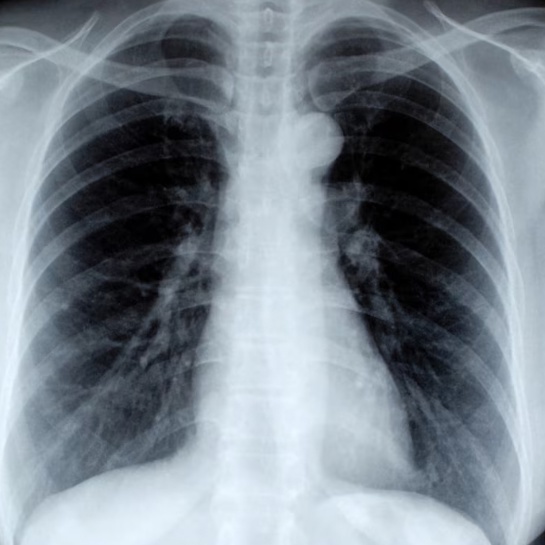

Флюорография: как часто нужно делать и зачем?

Флюорография - это рентгенологическое исследование легких. "Фотографировать" легкие нужно раз в год обязательно, даже в том случае, если никаких симптомов нет.

Почему? Потому что это исследование позволяет выявить туберкулез, пневмонию, онкологические заболевания легких, патологические процессы в легочной системе на самых ранних стадиях, тогда, когда никаких симптомов еще нет.